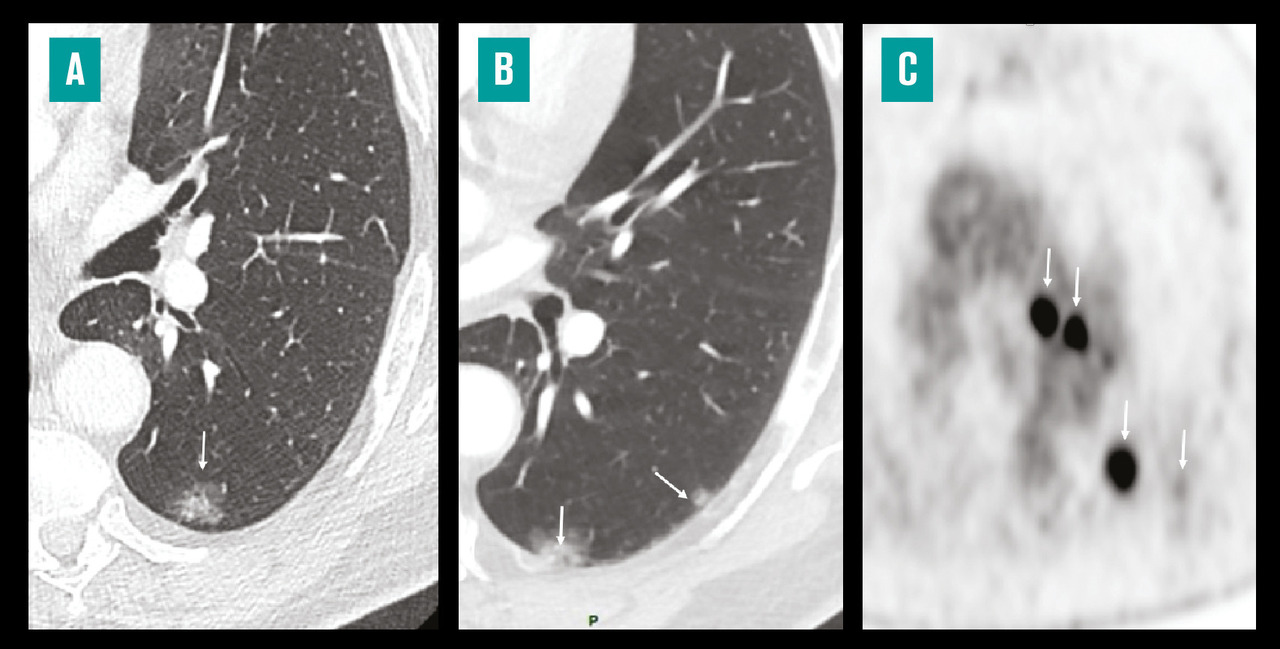

Outre le fait que la pratique de ce scanner est susceptible de sauver des vies (v. figure ), le dépistage des cancers du poumon par cette technique a d’autres avantages :

– le scanner LD générerait beaucoup de « faux positifs », qui nécessiteraient des examens parfois invasifs, coûteux, et dont la pratique générerait de l’anxiété. Le suivi volumétrique des nodules, comme nous l’a appris l’étude NELSON, permet de réduire considérablement ces « faux positifs » ;1